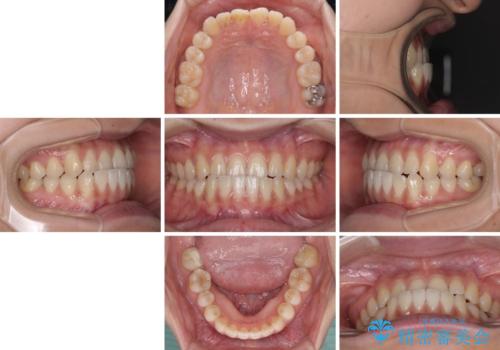

- 前歯の反対咬合を気にして来院された患者様です。

マウスピース矯正も提案しましたが、しっかりと使用する自信がないとのことで、ワイヤー装置により矯正治療を行うこととしました。

クロスバイト改善まではスムーズに進みましたが、その後は強い舌の突出癖によりオープンバイトの期間が長く続きました。

舌のトレーニングをしっかりと実施してもらい、何とか仕上げることができました。